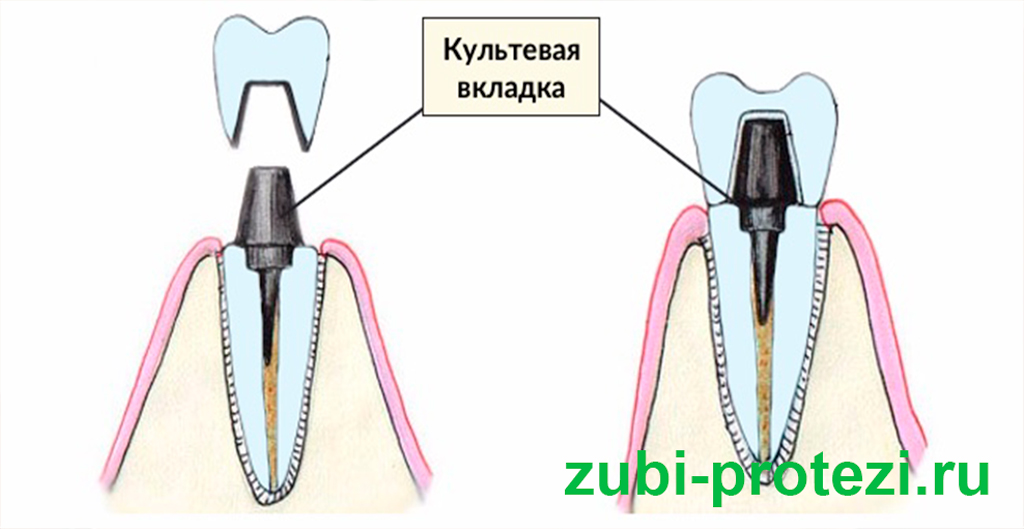

Культя зуба это

Культя зуба это 106 фото